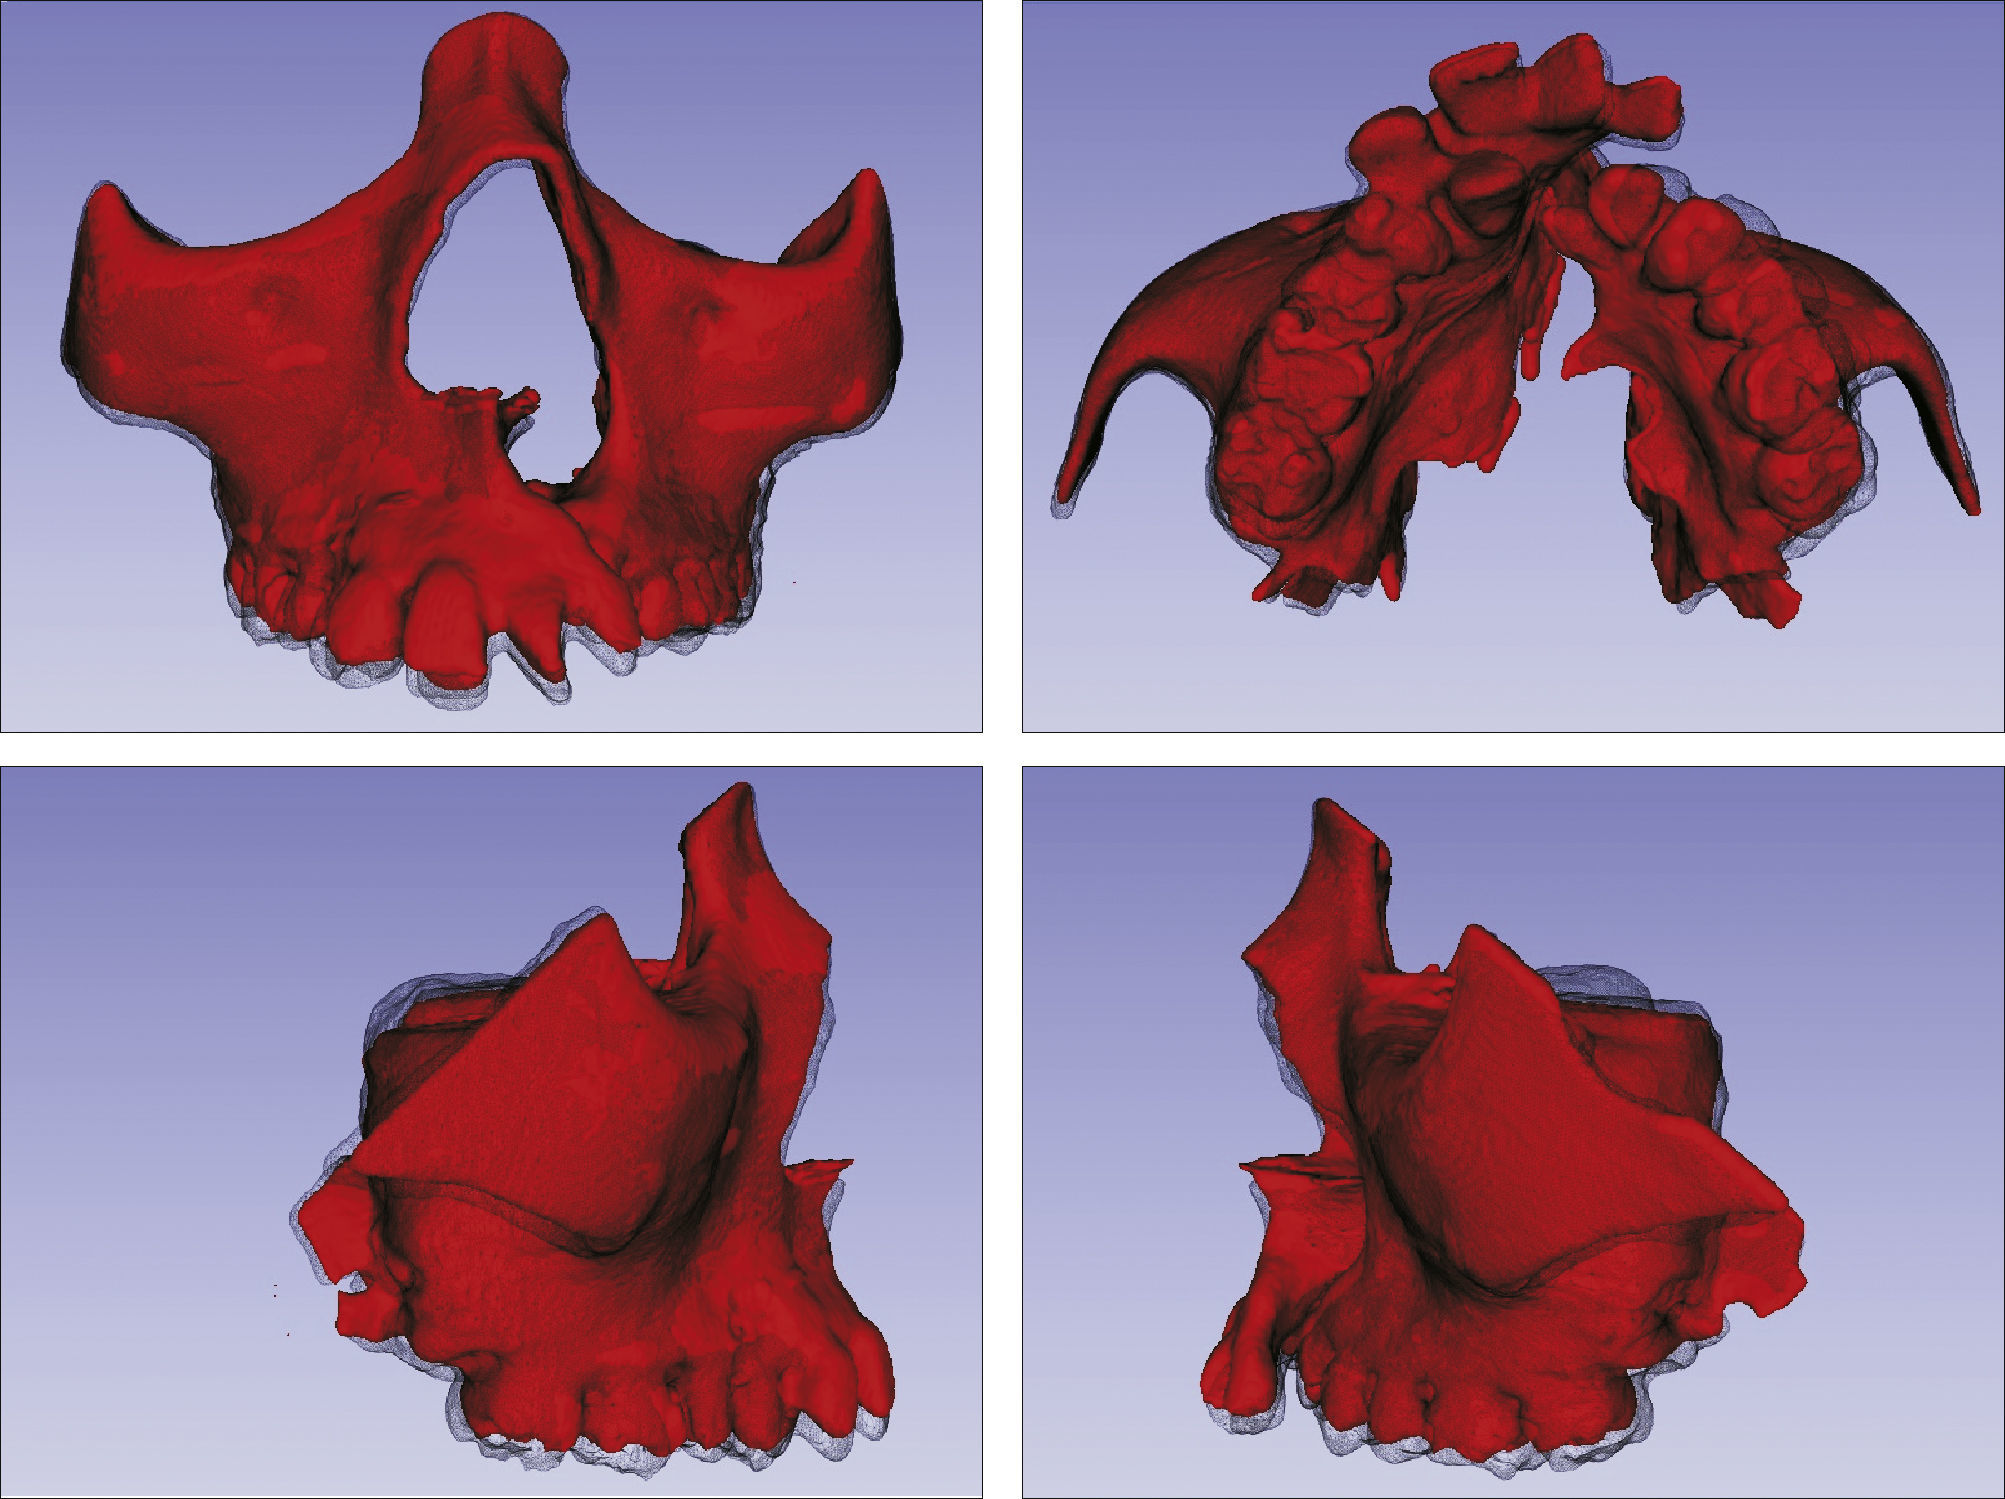

O surgimento e o aumento da acessibilidade da TCFC agregaram uma maior credibilidade ao diagnóstico clínico e às investigações científicas no estudo das deformidades craniofaciais19. Todavia, as informações 3D fornecidas pelas TCFC ainda vêm sendo rotineiramente analisadas de forma 2D, por medidas lineares em cortes ortogonais5,20. A construção e sobreposição de modelos virtuais 3D ainda é uma metodologia pouco difundida. Este estudo é um dos pioneiros que utiliza este método para avaliação de ERM em pacientes com fenda. A sobreposição baseia‐se na construção dos modelos virtuais 3D, utilizando o software SLICER21, pelos arquivos obtidos na TCFC, seguida pela sua justaposição, que utiliza a base do crânio como referência e a final obtenção dos métodos de medidas intitulados: sobreposição por semitransparência e mapa por códigos de cores22. A sobreposição por semitransparência revela uma análise qualitativa, em que o momento pós‐tratamento é retratado por uma malha preta translúcida, sobre o modelo inicial em vermelho (figs. 9 e 10). O aparelho em leque demonstrou um deslocamento de quase todos os dentes para vestibular e uma movimentação vestíbulo‐posterior do segmento menor (lado esquerdo [fig. 9]). O mapa por códigos de cores permite um complemento da análise visual, sendo que cada cor reflete uma alteração na posição das estruturas: azul – recuo; verde – estabilidade e vermelho – expansão. A intensidade da cor está diretamente relacionada à quantidade de movimentação. Todo o mapa é seguido por uma escala, com os valores em milímetros para cada cor (figs. 11 e 12). A observação feita na sobreposição por semitransparência do expansor em leque é confirmada no mapa por código de cores e nas medidas lineares. Uma menor porção de vermelho é visualizada em molares, quando comparada aos pré‐molares. O deslocamento para posterior e vestibular do menor segmento é constatado pela presença de azul na mesial dos dentes e vermelho nas eminências alveolares do lado em questão. Diferentes tonalidades de azul são vistas na cervical dos incisivos, possivelmente uma retroinclinação em decorrência da ausência de apoio mecânico no local. Para a quantificação das mudanças no posicionamento dentário, primeiramente identificou‐se, nos 3 cortes ortogonais, os pontos de referência para a medida (ponta da cúspide mésio vestibular dos primeiros molares superiores e ponta da cúspide dos caninos), tanto do lado direito como do lado esquerdo, utilizando o software ITK Snap23. Os pontos foram marcados com uma esfera de 0,5mm de diâmetro, identificando a posição 3D destas referências no espaço (fig. 13). A aferição das distâncias Euclidianas entre as esferas foi realizada com o auxílio da ferramenta Q3DC no programa SLICER23. O paciente A obteve um aumento de 3mm na distância intercanina e de 6mm na distância intermolar. Na elucidação do paciente que utilizou o disjuntor mini‐Hyrax invertido com BTP (B), observa‐se na sobreposição por semitransparência um deslocamento vestibular, principalmente dos pré‐molares e uma constância das demais áreas, achados corroborados no mapa por código de cores. A área que não está verde é a região de pré‐molares, vermelho por vestibular e azul por palatino, notando uma tonalidade entre verde e vermelho (amarelo) no corpo da maxila do lado menor (esquerdo). A oclusal dos molares, em vermelho, representa a erupção dos elementos.

Sobreposição com semitransparência dos modelos 3D do tratamento com o aparelho em leque. Antes da expansão representado por vermelho e após a expansão pela malha fina translúcida. Observa‐se um trespasse da malha preta para vestibular em molares, pré‐molares e canino, indicando que houve expansão em toda essa região.